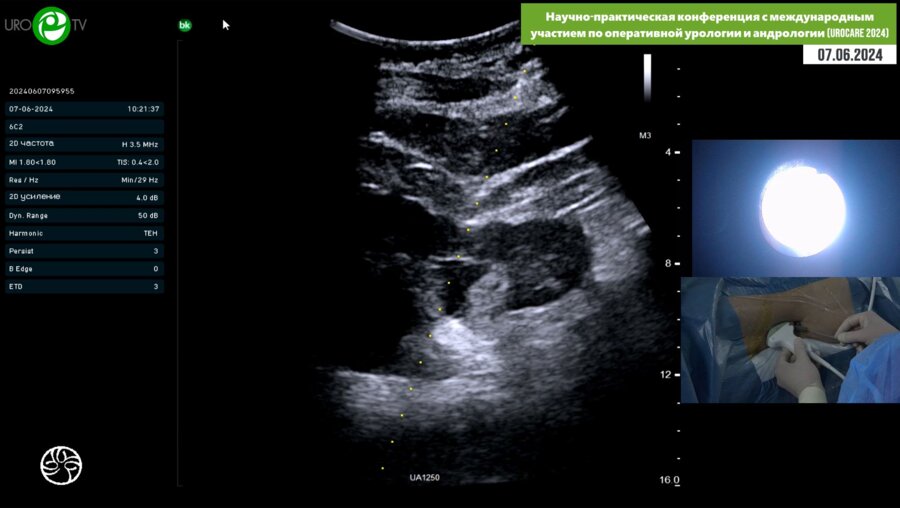

Научно-практическая конференция с международным участием по оперативной урологии и андрологии (UROCARE 2024)

06-07 июн 2024